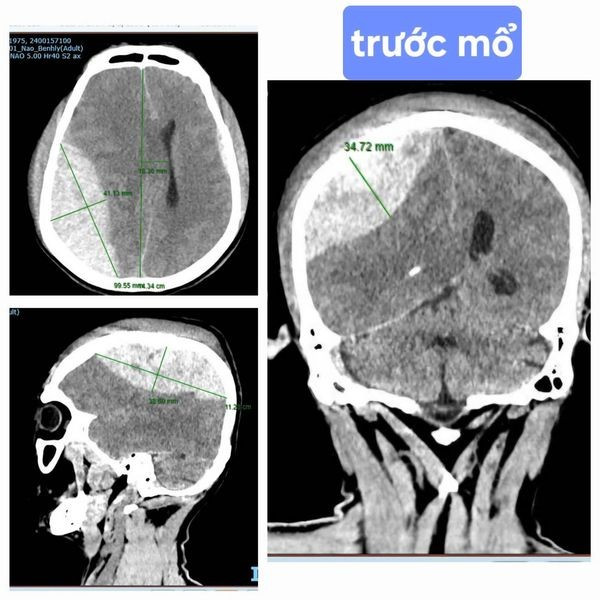

| Hình ảnh CT Scant cho thấy khối máu tụ ngoài màng cứng đỉnh phải 100ml, chèn ép não nhiều, đẩy lệch đường giữa 17mm - Ảnh BVCC |